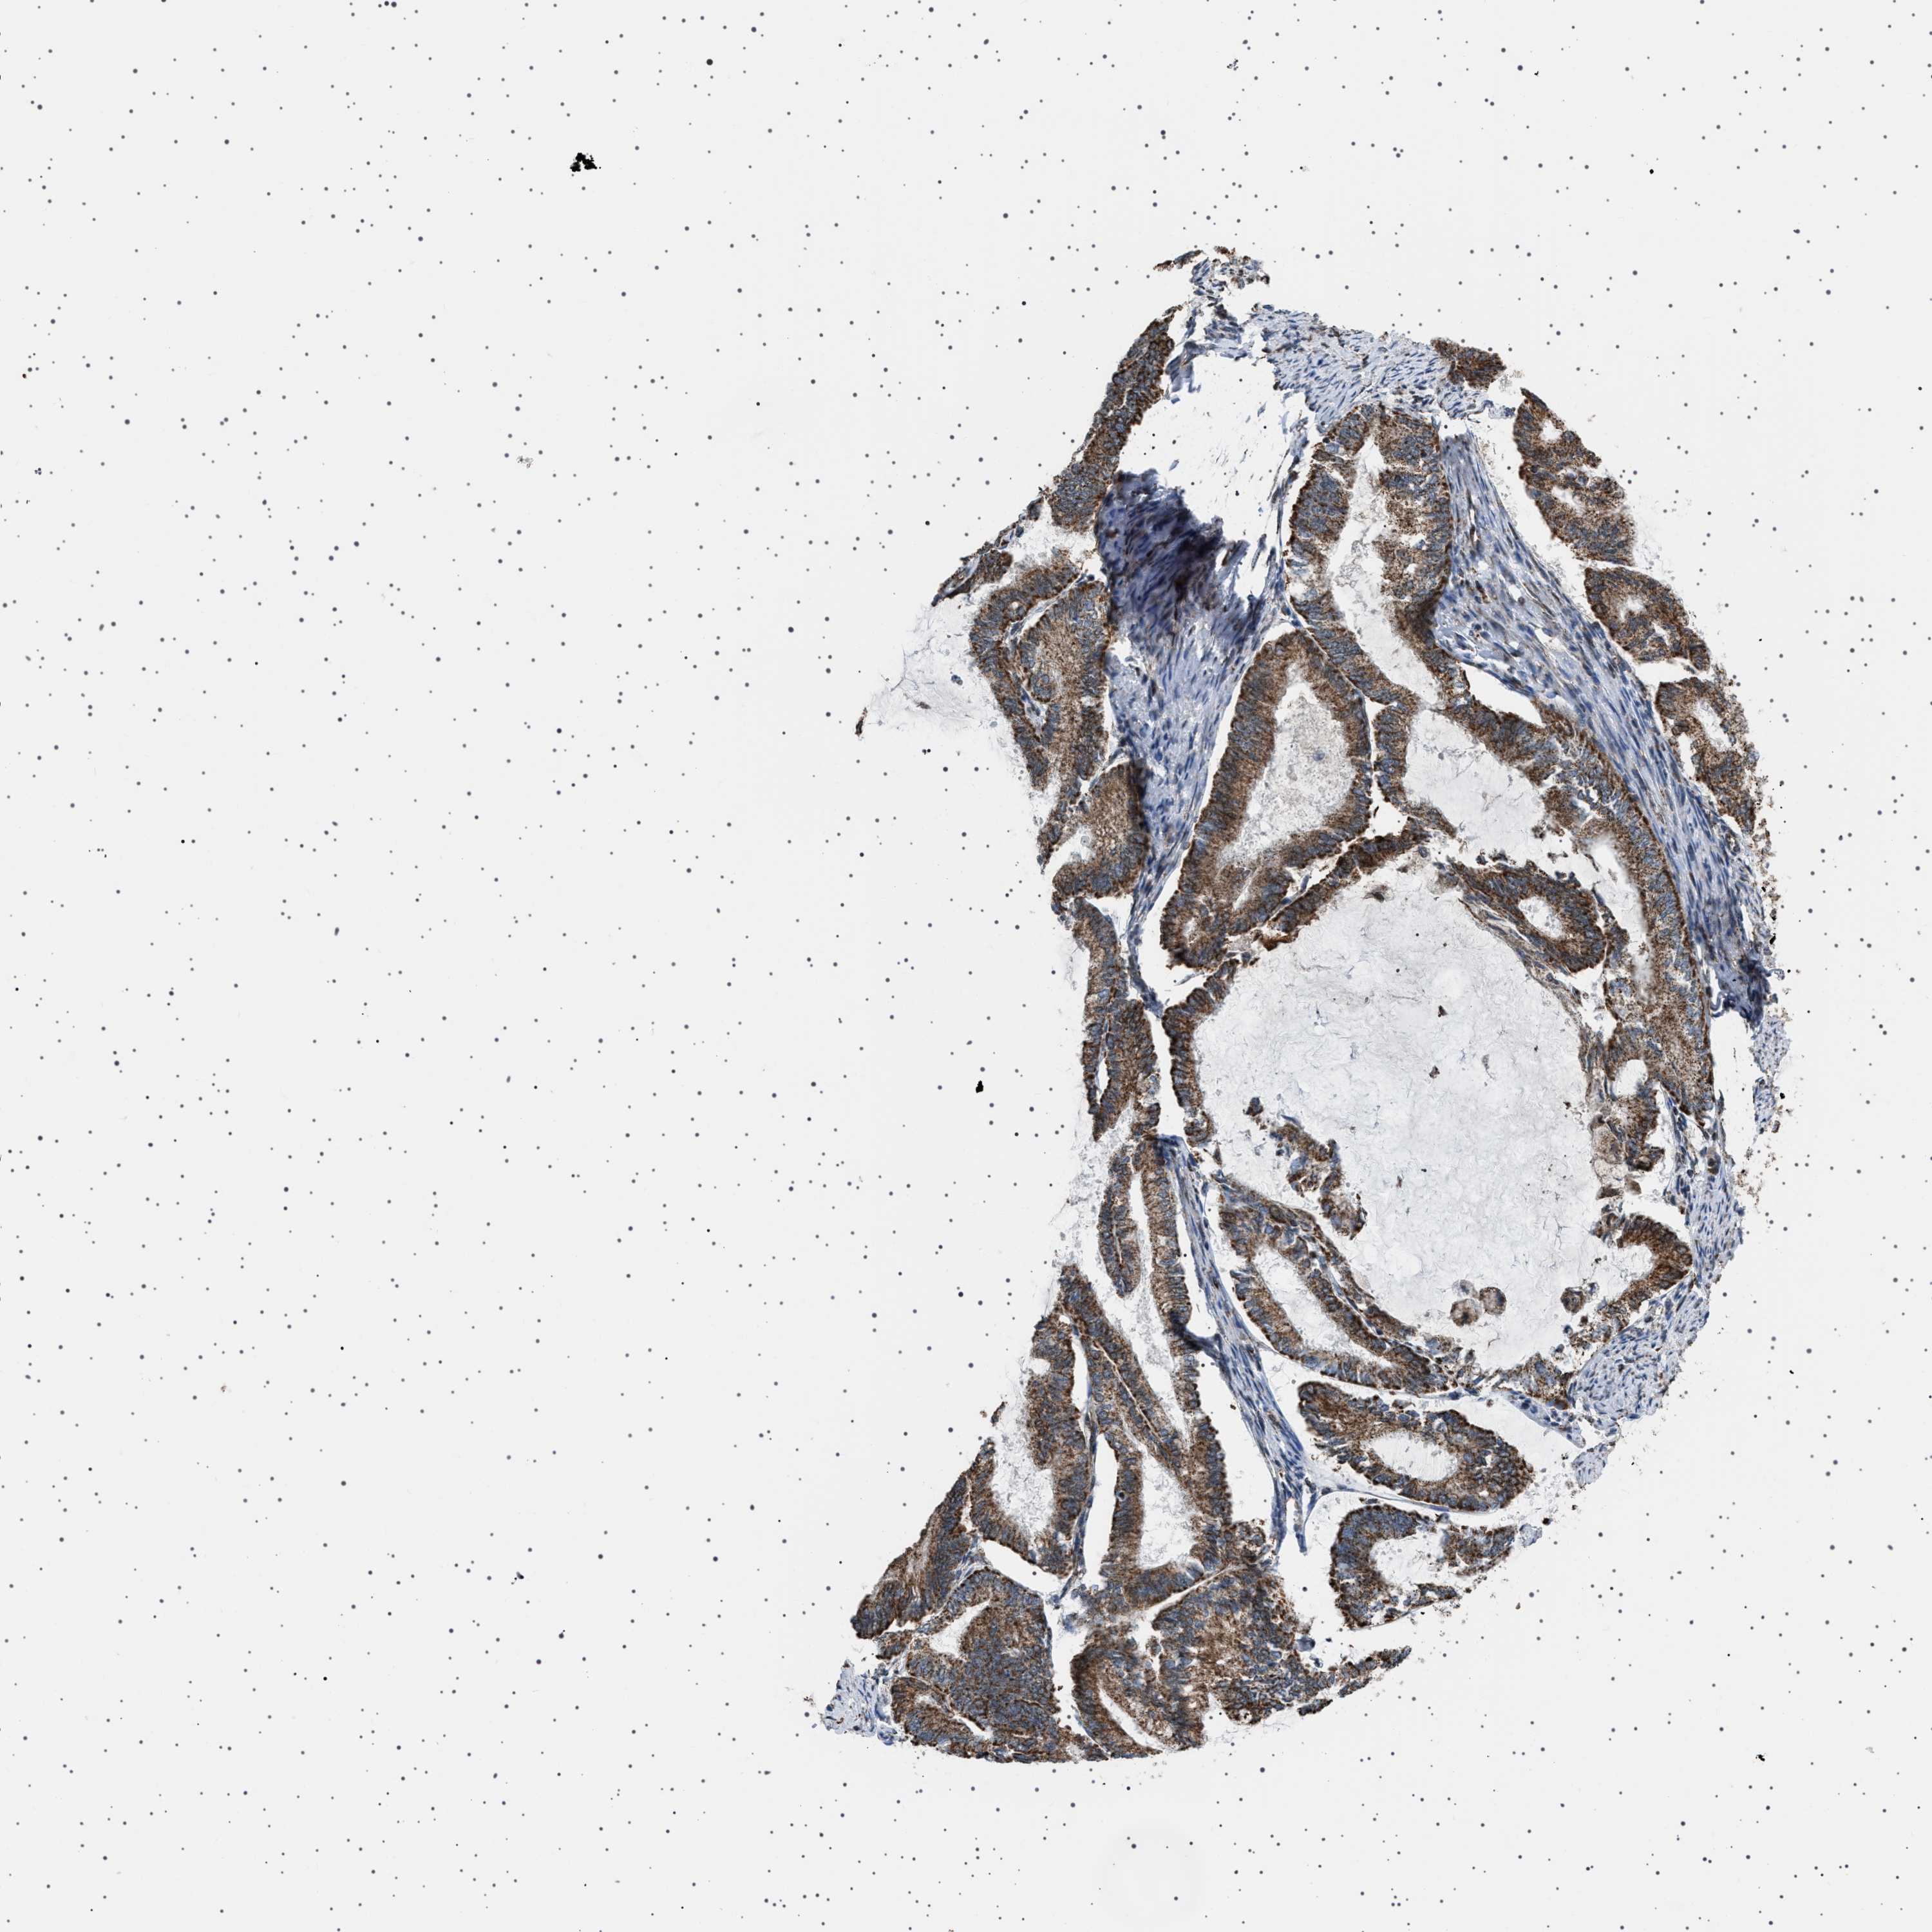

ENDOMETRIAL CANCER - Protein expressioni

A mouse-over function shows sample information and annotation data. Click on an image to view it in a full screen mode. Samples can be filtered based on level of antibody staining by selecting one or several of the following categories: high, medium, low and not detected. The assay and annotation is described here.

Note that samples used for immunohistochemistry by the Human Protein Atlas do not correspond to samples in the TCGA dataset.

Antibody stainingi

Antibody staining in the annotated cell types in the current human tissue is reported as not detected, low, medium, or high, based on conventional immunohistochemistry profiling in selected tissues. This score is based on the combination of the staining intensity and fraction of stained cells.

Each image is clickable and will lead to virtual microscopy that enables deeper exploration of all samples and also displays staining intensity scores, fraction scores and subcellular localization as well as patient and tissue information for each sample.

Antibody HPA017214

Staining

High

Medium

Low

Not detected

Intensity

Strong

Moderate

Weak

Negative

Quantity

>75%

75%-25%

<25%

None

Location

Nuclear

Cytoplasmic/membranous

Cytoplasmic/membranous,nuclear

Adenocarcinoma, NOS